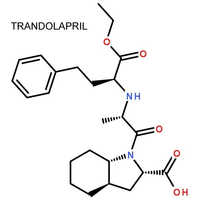

| रासायनिक नाम | Thymopentin |

| रासायनिक नाम | Thymopentin |